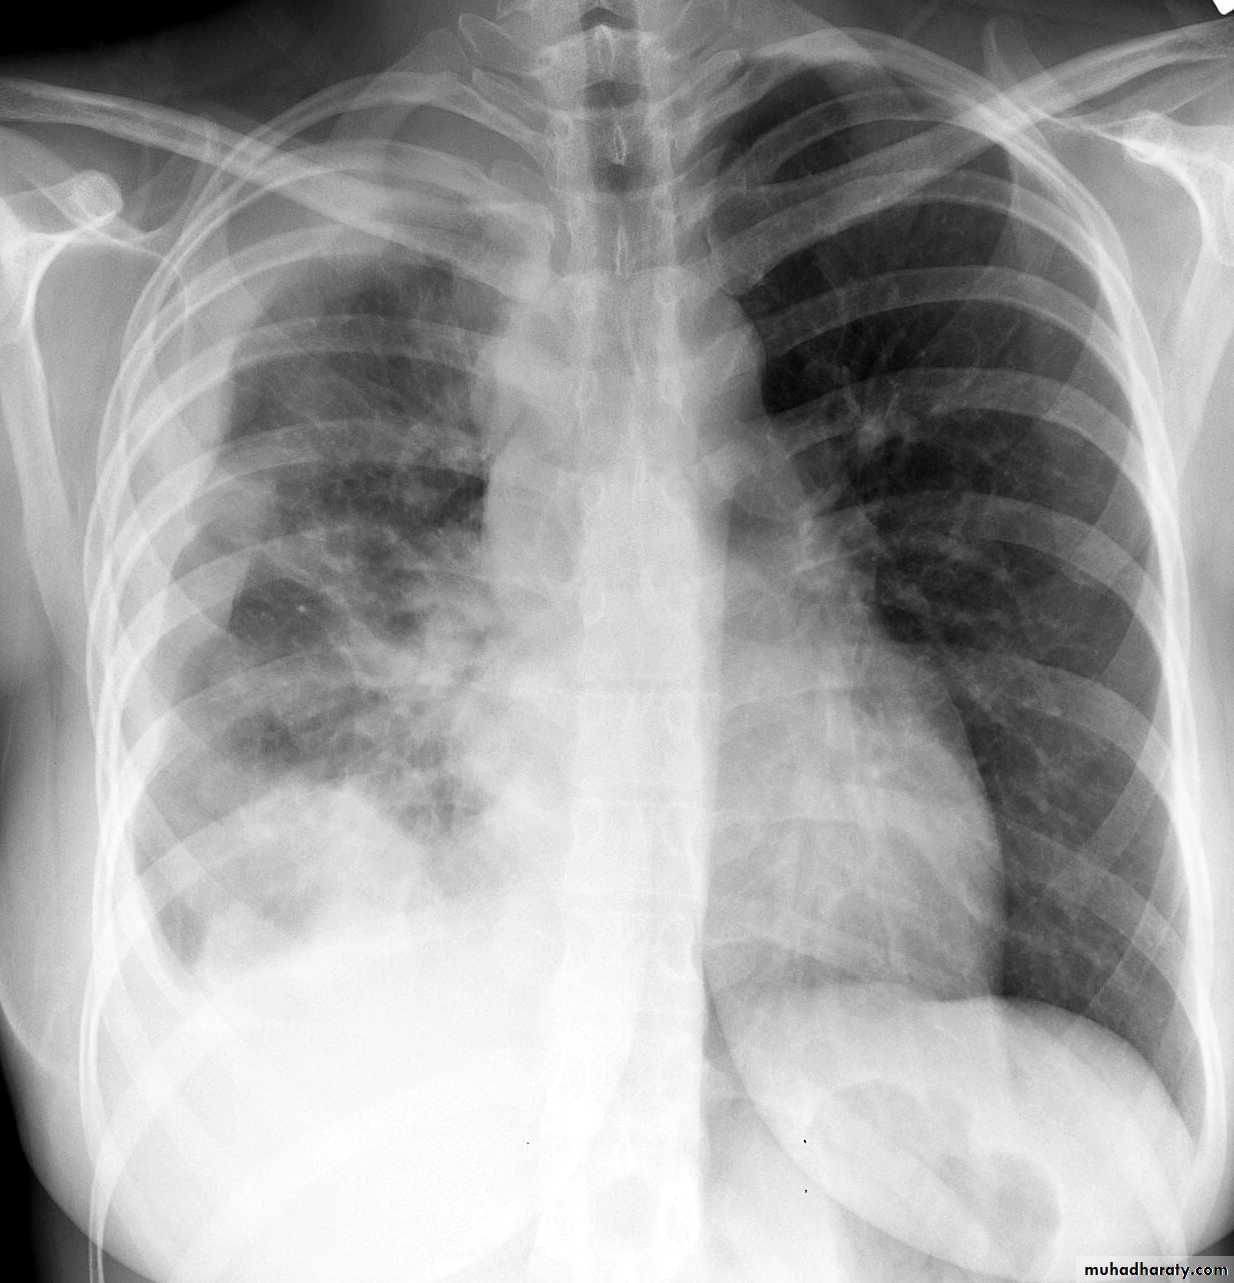

CXR:

closed Pneumothorax

Tension Pnenmothorax

Massive effusion

Whole lung atelectasisEmpyema